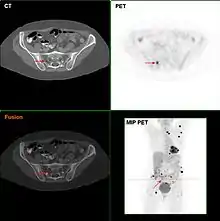

Metastatic melanomas can be detected by X-rays, CT scans, MRIs, PET and PET/CTs, ultrasound, LDH testing and photoacoustic detection.[88] However, there is lack of evidence in the accuracy of staging of people with melanoma with various imaging methods.[89]

It is common for patients diagnosed with melanoma to have chest X-rays and an LDH test, and in some cases CT, MRI, PET, and/or PET/CT scans. Although controversial, sentinel lymph node biopsies and examination of the lymph nodes are also performed in patients to assess spread to the lymph nodes. A diagnosis of melanoma is supported by the presence of the S-100 protein marker.